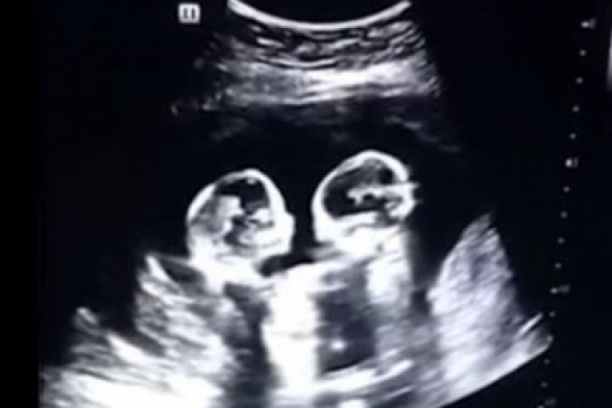

19:00 09.07.2022 ŽELELA JE JOŠ JEDNO DETE, A ONDA JE OTIŠLA NA ULTRAZVUK! Ovome se nije nadala ni u najluđim snovima! (FOTO+VIDEO)